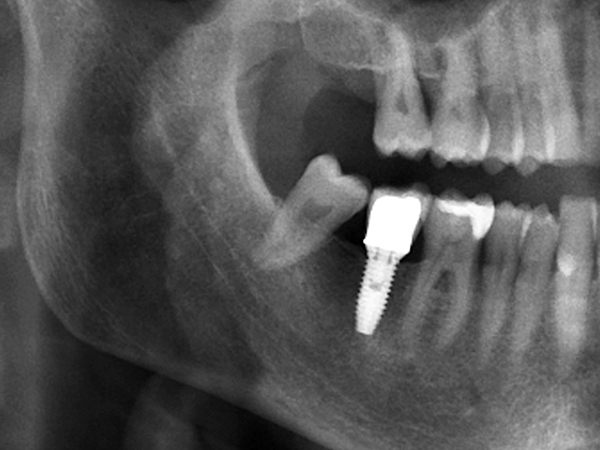

[임플란트] 타치과 임플란트 실패 후 재식립 사례

[임플란트] 전악 임플란트 식립사례